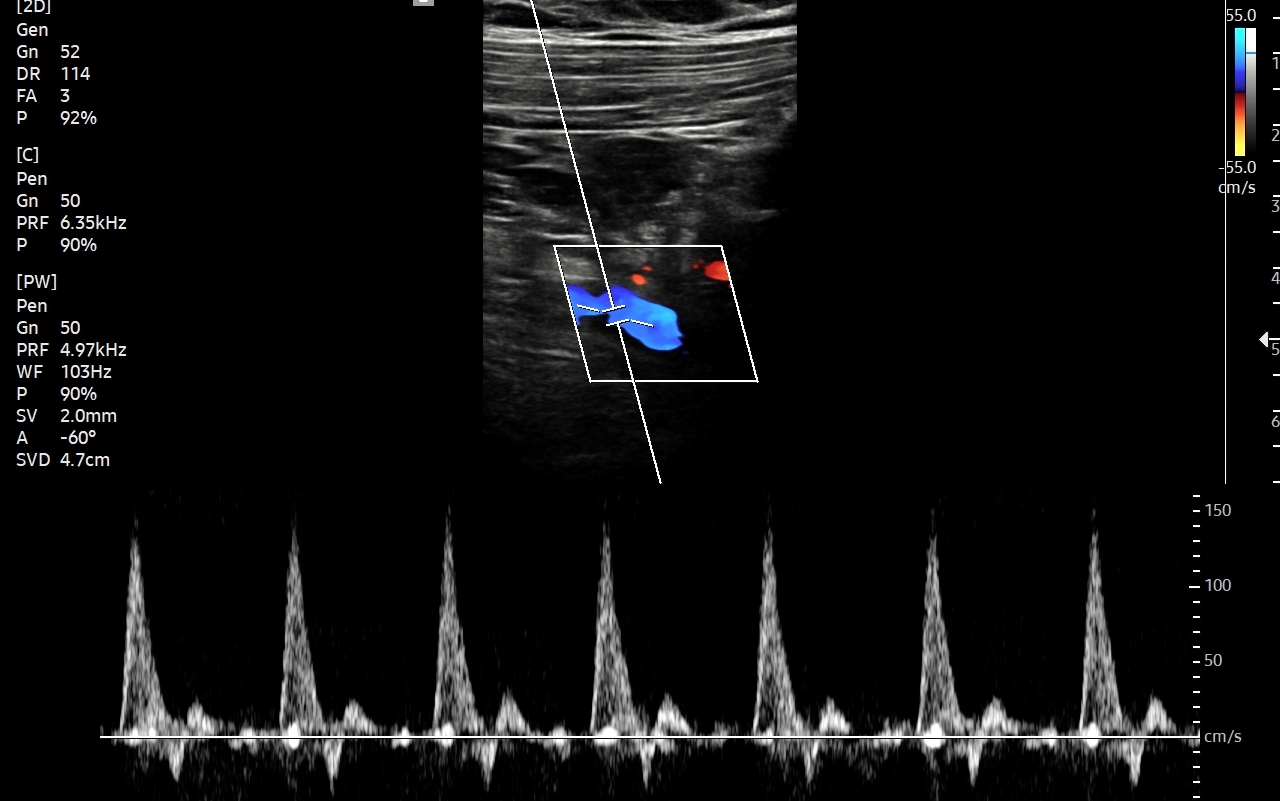

Badanie USG Doppler tętnic szyjnych i kręgowych, określane również jako badanie USG tętnic dogłowowych, to najczęściej wykonywane badanie diagnostyczne w układzie tętniczym. Wynika to z faktu, iż wymienione naczynia doprowadzają krew do jednego z najważniejszych organów człowieka, tj. mózgu, a choroby lokalizujące się w tętnicach dogłowowych mogą być źródłem różnorodnych objawów neurologicznych począwszy od zaburzeń pamięci i widzenia, poprzez bóle i zawroty głowy, aż do zgonu na tle nagłego udaru niedokrwiennego. W trakcie standardowego badania USG tętnic dogłowowych oceniane po obu stronach są tętnice szyjne wspólne, wewnętrzne, zewnętrzne oraz tętnice kręgowe. Badanie niejednokrotnie rozszerza się o specjalistyczną ocenę USG łuku aorty, USG tętnic podobojczykowych, USG tętnic skroniowych, czy o badanie USG Doppler przezczaszkowy.

Badanie USG Doppler tętnic wewnątrzczaszkowych (ang. TCCD, transcranial color-coded Doppler), nazywane także Dopplerem przezczaszkowym jest naturalnym rozszerzeniem i uzupełnieniem badania dopplerowskiego tętnic dogłowowych zewnątrzczaszkowych. Badanie polega na obrazowaniu przy użyciu dedykowanej sondy poprzez tzw. okno skroniowe czaszki głównych naczyń tętniczych mózgu, tj. koła Willisa, tętnic mózgowych przednich, środkowych i tylnych po obu stronach. Badanie TCCD umożliwia wykrycie wybranych wewnątrzczaszkowych patologii naczyniowych takich jak tętniaki, malformacje naczyniowe, zwężenia i niedrożności poszczególnych tętnic mózgowych, spazm naczyniowy, a także pozwala na ocenę kierunku przepływy krwi w kole Willisa mózgu, co  jest przydatne przy diagnostyce zespołu podkradania lub w ocenie po przebyciu udaru mózgowego.